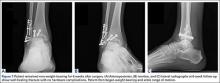

Next, the lateral malleolus was open-reduced, and fixation was achieved using a standard interfragmentary lag screw and a lateral neutralization plate technique (Figure 6). After surgery, the patient was immobilized in a posterior splint with side gussets. Two weeks later, the incisions were healing well, and the tibialis posterior tendon was functioning normally. The sutures were removed, the patient was transitioned to a controlled ankle movement (CAM) boot, and ankle and subtalar range-of-motion exercises were initiated. The patient remained non-weight-bearing for 6 weeks. Radiographs 6 weeks after surgery showed healing fractures with stable hardware (Figure 7). The patient demonstrated 5/5 strength of the tibialis posterior tendon without subluxation or dislocation. There was no tenderness to palpation over the fracture sites or tibialis posterior tendon. The patient began progressive weight-bearing in a CAM boot and physical therapy for range of motion and strengthening.